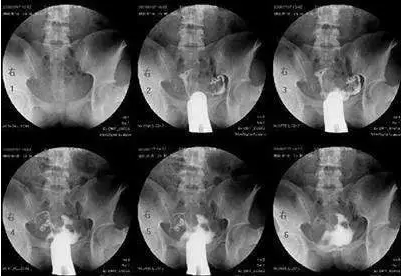

當(dāng)然,以上說(shuō)的都是可能性的癥狀,并不代表有這些癥狀就一定是輸卵管有問題的。如果有這些癥狀,要適度警惕一下。當(dāng)然,您也不需要太擔(dān)憂,最好還要結(jié)合多種情況綜合考慮,如果實(shí)在不放心,可以去醫(yī)院做做輸卵管造影術(shù),或者做輸卵管通水、腹腔鏡檢查、輸卵管鏡檢查等。

最常用的是輸卵管碘油造影(HSG)

醫(yī)生會(huì)根據(jù)不孕的時(shí)間、可能的原因,來(lái)選擇是否需要做造影。

造影的時(shí)間一般在月經(jīng)干凈后3天到排卵之前,造影前不要有性生活,白帶檢查正常等等。造影后1周禁性生活,當(dāng)月最好不要嘗試懷孕。

不過現(xiàn)在的造影劑比較先進(jìn),一般代謝很快,假如不小心當(dāng)月懷上,多數(shù)也沒有問題。保險(xiǎn)一點(diǎn),等下次月經(jīng)來(lái)過再試孕。